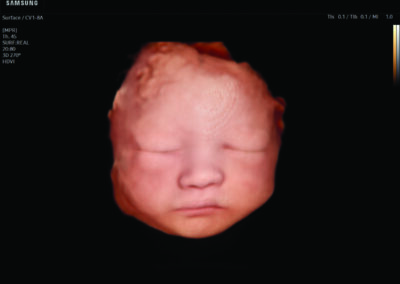

Comprehensive, advanced and expert MFM care for high-risk pregnancies